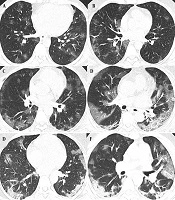

Assessing Machine Learning Classifiers in COVID-19: The Role of Clinical, Laboratory, and Radiological Features in Predicting Oxygen Saturation

Mostafa ShahidzadeORCID*,

Ramezan Jafari,

Nematollah Jonaidi Jafari,

Fateme Salmanizadegan,

Omid Teymouri,

Maryam Sabouri

,et al.

|

Final Published